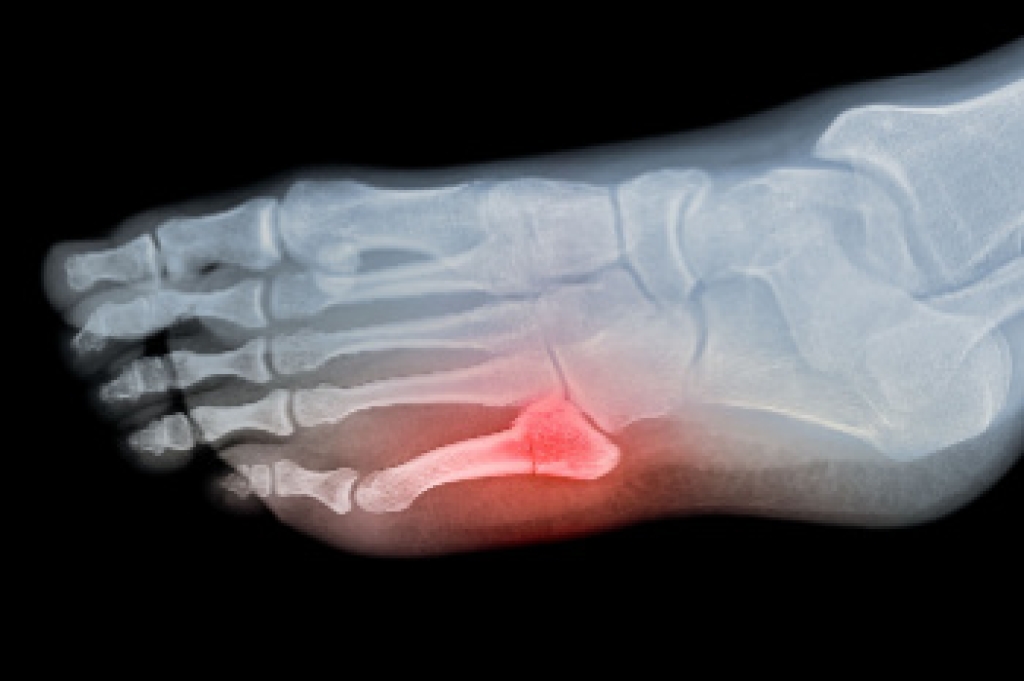

A broken ankle refers to a fracture in one or more of the bones that make up the ankle joint. It can result from trauma such as a fall, sports injury, or an accident that forces the joint beyond its normal range of motion. Symptoms include sharp pain, swelling, bruising, inability to bear weight, and visible deformity. Risk factors include high-impact activities, weak bones, improper footwear, and poor balance. A podiatrist can assess the injury through physical examination and imaging, then recommend appropriate treatment, such as immobilization, orthotics, or referral for surgical care. With expert guidance, a podiatrist helps ensure proper healing, pain management, and rehabilitation to restore strength and mobility in the affected ankle. If you have symptoms of a broken ankle, it is suggested that you contact this type of doctor who can offer appropriate treatment solutions.

A broken ankle is experienced when a person fractures their tibia or fibula in the lower leg and ankle area. Both of these bones are attached at the bottom of the leg and combine to form what we know to be our ankle.

When a physician is referring to a break of the ankle, he or she is usually referring to a break in the area where the tibia and fibula are joined to create our ankle joint. Ankles are more prone to fractures because the ankle is an area that suffers a lot of pressure and stress. There are some obvious signs when a person experiences a fractured ankle, and the following symptoms may be present.

If you suspect an ankle fracture, it is recommended to seek treatment as soon as possible. The sooner you have your podiatrist diagnose the fracture, the quicker you’ll be on the way towards recovery.